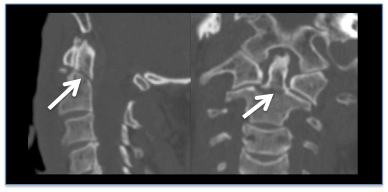

Reconstrução em tomografia computadorizada (TC), demonstrando uma fratura do odontoide sem desvio

Do acervo pessoal de Michael G. Fehlings